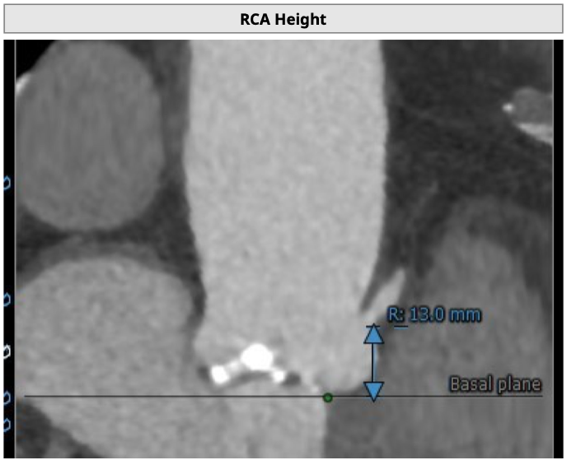

主动脉根部评估

CT 数据显示该患者为Type1型二叶式主动脉瓣

无冠瓣钙化严重,HU850:448mm³

瓣环水平夹角46度